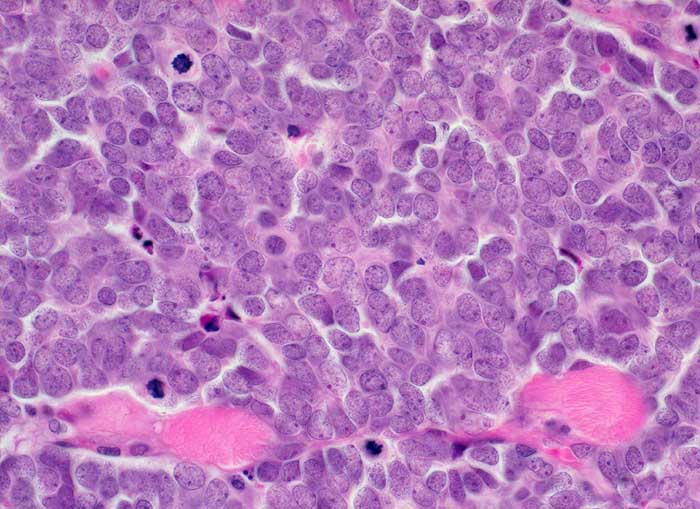

l/ Merkelzellkarzinom

Merkelzellkarzinom

Das Merkelzellkarzinom ist ein neuroendokrines Karzinom ausgehend von den Merkelzellen der Haut. Die Ausstriche sind zellreich. Die monomorphen zytoplasmaarmen Zellen liegen einzeln oder in lockeren Verbänden. Die Kerne sind fragil, rund bis oval und hyperchromatisch. Das Chromatin zeigt ein Pfeffer und Salz Bild. Die Unterscheidung von der Metastase eines kleinzelligen Bronchuskarzinoms oder von einem Lymphom kann immunzytochemisch erfolgen. Merkelzellkarzinome zeigen eine charakteristische punktförmige zytoplasmatische Positivität für CK20 und sind negativ für TTF1, BerEP-4 und CD45.